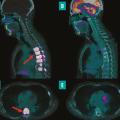

La médecine nucléaire, spécialité d’imagerie médicale en plein essor depuis cinquante ans, joue aujourd’hui un rôle important dans de nombreuses spécialités, telles que l’oncologie, la cardiologie ou encore la neurologie. Le principe de la médecine nucléaire repose sur l’utilisation de sources radioactives non scellées pour…

Dans le cadre de la prise en charge des cancers, la radiothérapie joue un rôle central, constituant une modalité de traitement utilisée chez plus de la moitié des patients à un moment de leur parcours thérapeutique. Bien qu’elle soit une composante essentielle des soins oncologiques, ses aspects techniques et ses évolutions récentes…